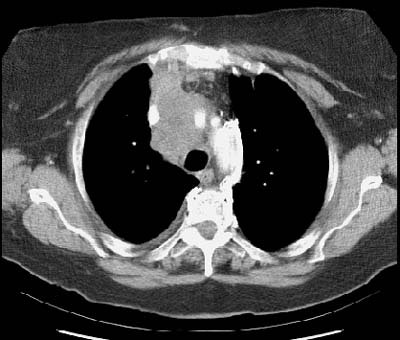

Example 2: False-negative CT exam -- this patient had an adenocarcinoma in the right upper lobe that measured less than 3 cm in size (T1 lesion). The ipsilateral mediastinal nodes identified by staging CT were not pathologic by size criteria. The surgical team elected to proceed to thoracotomy without mediastinoscopy. At surgery, the small right paratracheal nodes which measured less than 1 cm where found to contain microscopic foci of tumor (N2 nodes). The patient was staged histopathologically as T1N2M0 (Stage IIIA).